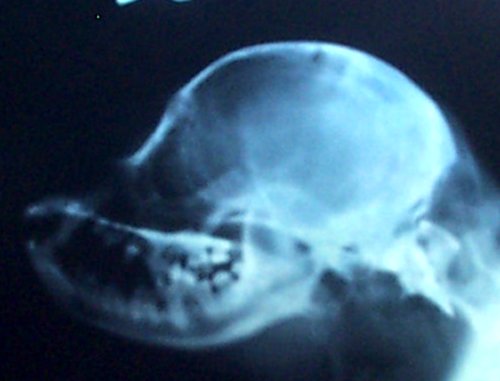

The skull x-ray of a dog with a full cerebellum is below that on

the left and the skull x-ray of a dog with a crushed cerebellum

is shown on the right. You can easily see there is a distinct

difference in the shape of the back of the skull between the two

and why the cerebellum ends up crushed. The most distinct

difference, besides the fact that the skull on the right is

shorter from front to back, is that the occiput sticks out in

the skull x-ray on the left. In the right, that occiput is still

there, but it is more downsloped and blends in with the back of

the skull to the point you can barely see it--almost like

someone took a hammer to the occiput and smashed it in.